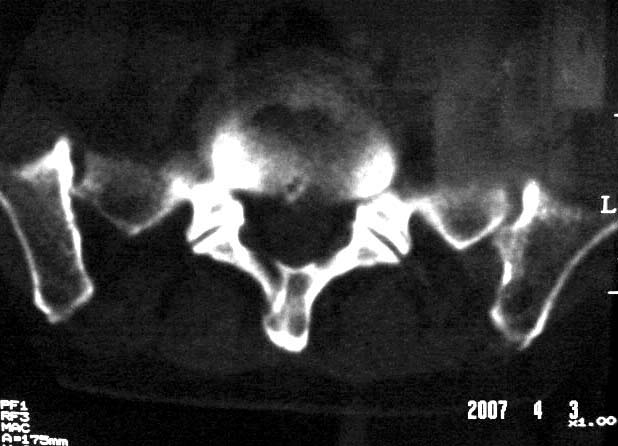

行腰椎间盘检查时,发现左侧髂骨后缘一类圆形低密度影,ct值约负43hu。

考虑骨内脂肪瘤或局限性异常脂质聚集,不排除转移瘤骨质破坏

左髂骨后缘骨脂肪瘤?

左髂骨后缘髓内囊性低密度影ct值-43,考虑髂骨髓内脂肪瘤。应该是少见病变,但跟骨脂肪瘤有过报道。

既然是负值,那么考虑骨纤维结构不良、骨囊肿就不太合适了。由战友考虑骨髓窦,个人认为觉得也不妥。理由很简单,骨髓窦是一种骨骨松质内小梁发育稀少或缺失形成的空腔,因而张力较小,形态可以不规则。而本例病变形态规则呈圆形,且边缘轻度硬化,这些度不符合骨髓窦的特征。所以本例应该考虑骨内脂肪瘤

支持左髂骨后缘骨良性囊性病变。左髂骨后缘骨脂肪瘤?